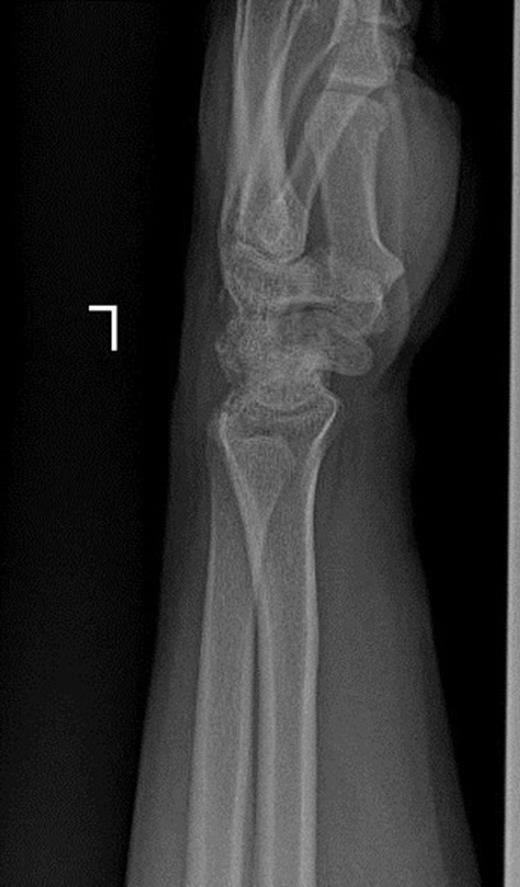

A 19-year old right hand dominant worker man presented after falling from height of about 6 meters onto his left hyperextened wrist. He was a multiple-injured case with closed fractures of femoral shaft and proximal phalanx of left second finger. In exam, wrist swelling was generally moderate with subtle deformity and ecchymosis in volar part. Range of wrist motion was very tender. A thorough serial neurovascular examination showed progressive paresthesia in median nerve territory checked by two points discrimination. Taken X-ray disclosed trans-scaphoid dorsal perilunate fracture dislocation and avulsion fracture of ulnar styloid. Excessive displacement of the lunate to middle third of the forearm and proximal scaphoid with multiple bony fragments to distal third was obvious (Figure 1a & 1b).

Posteroanterior and lateral X-rays of left wrist show perilunate fracture dislocation with excessive proximal displacement of lunate and proximal scaphoid. Loss of carpal height with broken Gilula’s arcs is obvious.